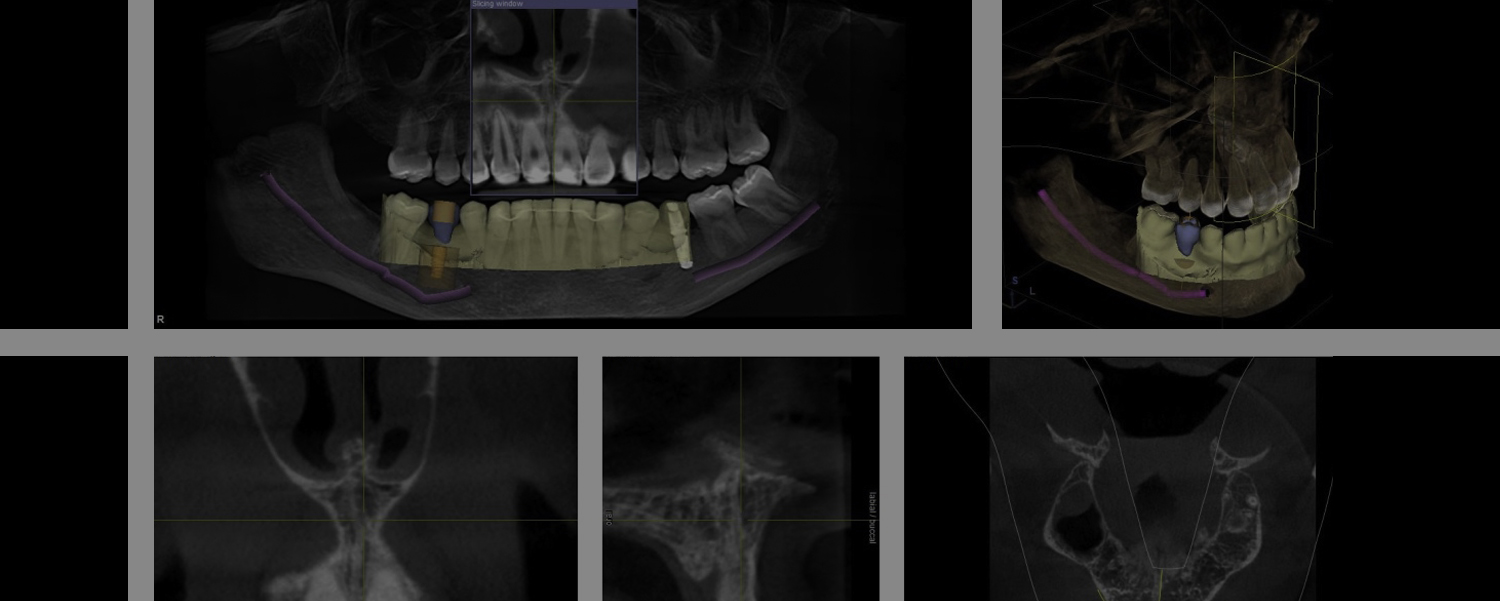

- 1.Intra oral digital video scan of the area of missing teeth in the mouth.

- 2.3D xray of the mouth.

- 3.3D plan of the implant type and location in the mouth.

- 4.Implant placement in the mouth using a 3D planned surgical guide.